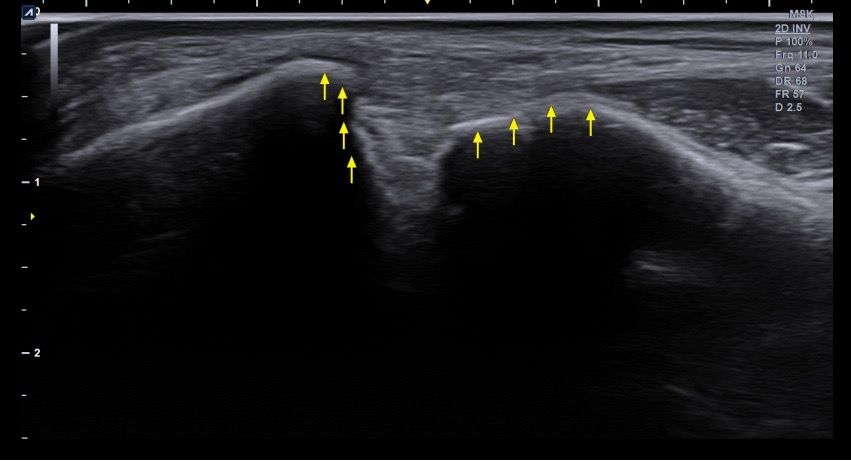

복숭아뼈 미세골절 초음파 사진 관련 질문

발목 접지른 후 치료받는 중인데요 복숭아뼈 미세골절이라고 하셨네요 3월 1일 다친뒤네 3월7일 병원방문후에 위에 초음파랑 엑스레이 촬영했고요 그뒤 반깁스 중입니다. 위에 엑스레이 상에선 안나오는데 초음파 사진에선 미세골절이 맞을까요? 골절이 경미한 수준인지 아니면 중한 건지 궁금합니다 그리고 다음주에 병원 방문 후 초음파 또 촬영하기로 했는데 그때 반깁스도 풀 수 있을까요??

• 4번 째 사진

약간의미세골절을 의심할 수 있는 상태로 보이는데요, 우선은 치료계획대로 진행하시는 것이 좋겠습니다.

미세골절인 경우에도 약2-4주의 회복기간이 필요할 수 있으므로, 경과를 관찰하며 불편감이나 통증이 있는 경우에는 유지하시는 것이 좋겠습니다.

발목의 복숭아뼈에 미세골절이 의심되는 경우, 엑스레이에서는 미세골절이 잘 보이지 않을 수 있습니다. 엑스레이는 큰 골절을 잘 확인하지만, 미세한 골절이나 염증 반응은 잘 나타나지 않기 때문이죠. 초음파는 조직의 변화를 보다 민감하게 감지할 수 있기 때문에, 미세골절을 발견하는 데 도움을 줄 수 있습니다. 초음파에서 미세골절이 확인되었다면, 이는 경미한 골절일 가능성이 높아요. 하지만 골절의 정확한 상태나 치유 과정을 판단하려면 정밀 검사가 필요하죠

미세골절의 치료는 시간이 필요하며, 반깁스를 착용하는 이유는 발목에 가해지는 부담을 줄이고, 골절 부위의 안정화를 돕기 위함입니다. 다음 병원 방문 시 초음파 촬영을 통해 골절의 치유 상태를 확인한 후, 의사가 반깁스를 풀어도 될지 결정할 듯 해요. 만약 골절이 잘 치유되었고 통증이 없다면 반깁스를 풀고 재활 운동을 시작할 수 있을 거구요. 하지만 치유가 더 필요한 경우에는 여전히 반깁스를 착용하거나 다른 치료 방법이 필요할 수 있겠죠